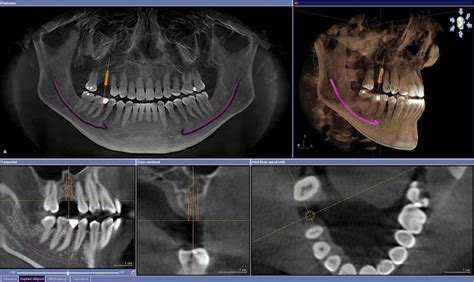

El TAC bucal sirve para hacer un completo estudio radiológico de la boca del paciente, ya que permite obtener imágenes de sus estructuras dentales y óseas. Esta tecnología revolucionaria permite a los dentistas y cirujanos maxilofaciales visualizar con precisión los tejidos duros y blandos de la boca, lo que les permite diagnosticar con mayor exactitud una variedad de condiciones, desde caries dentales hasta problemas de los senos paranasales.

El TAC dental sirve para tomar imágenes tridimensionales de las estructuras nerviosas, los dientes y los huesos craneofaciales, es una prueba diagnóstica. Cuando las radiografías dentales o faciales no son suficientes, se realiza el TAC dental. El TAC dental no se usa en cualquier procedimiento dental, se utiliza en tratamientos concretos.

A diferencia de las radiografías dentales convencionales, que solo proporcionan imágenes bidimensionales, el TAC dental ofrece imágenes tridimensionales de alta resolución. Esto significa que los profesionales de la salud dental pueden examinar cada estructura desde diferentes ángulos, lo que les brinda una comprensión más completa de la anatomía bucal de un paciente.

- Colocación de Implantes: Con el TAC mandibular y maxilar podemos medir la anchura, altura y espacio disponible para insertar los implantes. Estudiar las estructuras óseas es esencial para determinar la posición exacta del tornillo, además de asegurar el éxito de la cirugía. La planificación de la cirugía guiada por ordenador combinada con la carga inmediata permite recuperar todos los dientes en un día. El CBCT permite identificar la mejor vía para el acceso quirúrgico. Reduciendo así el riesgo de lesiones neurológicas, dentales. El TAC dental nos da la opción de colocar “virtualmente” los implantes gracias a los diferentes software que existen. Esto nos asegura que a la hora de la intervención el cirujano sepa con mucha seguridad cual es lugar más apropiado. También nos facilita que en intervenciones más complejas la tasa de éxito aumente. Antes de proceder a la colocación de uno o varios implantes dentales, necesitaremos saber si tu mandíbula cuenta con la cantidad y densidad suficiente de hueso como para darle soporte.